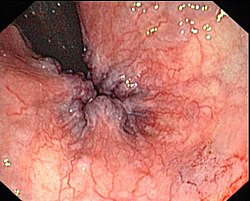

Daxili babasilin mərhələləri

MərhələDiaqramRəsm

1Endoskopik görüntü